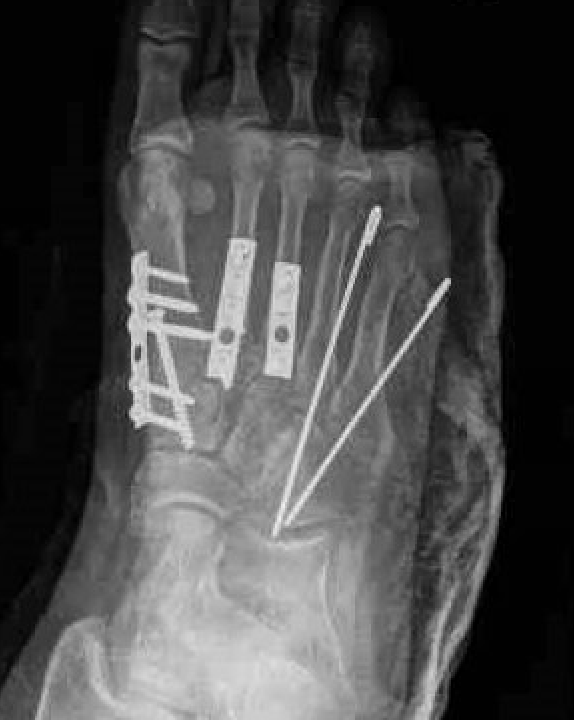

1st, 2nd & 3rd TMT joints

- trans-articular screw fixation

- bridge plate fixation

- primary arthrodesis

4th & 5th TMT joints

- consider K wire fixation

Screw fixation 1st and 2nd TMT with K wire fixation 3rd / 4th / 5th

Bridge plating of 1st, 2nd, 3rd & 4th TMT with screw fixation of Lisfranc joint

Fusion of 1st TMT, plating of 2nd and 3rd TMT, K wire stabilization of 4th and 5th TMT